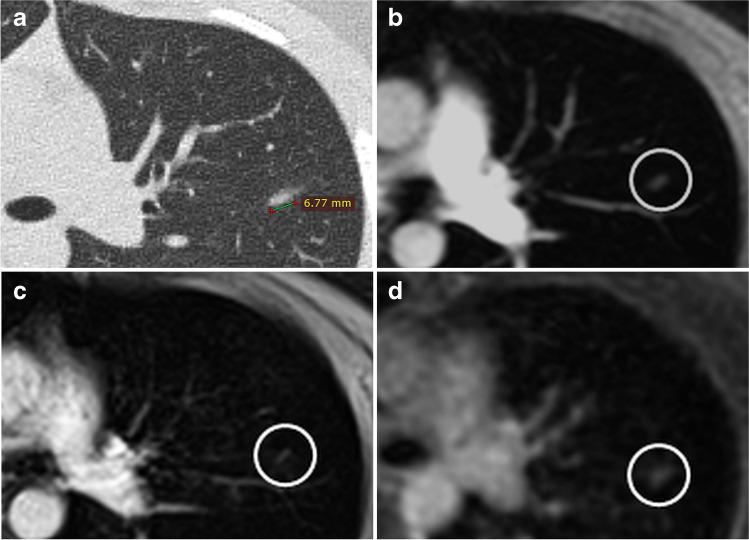

Twenty-three patients with proven oncologic disease (14 male, 9 female; mean age 9.0 + / - 5.4 years) received 35 low-dose CT and MRI examinations of the lung. The MRI protocol (1.5-T) included the following post-contrast sequences: two-dimensional (2D) incoherent gradient echo (GRE; acquisition with breath-hold), 3D volume interpolated GRE (breath-hold), and 3D high-resolution radial UTE sequences (performed during free-breathing). Images were evaluated by considering image quality as well as distinct diagnosis of pulmonary nodules and parenchymal areal opacities with consideration of sizes and characterisations.

The UTE technique showed significantly higher overall image quality, better sharpness, and fewer artefacts than both other sequences. On CT, 110 pulmonary nodules with a mean diameter of 4.9 + / - 2.9 mm were detected. UTE imaging resulted in a significantly higher detection rate compared to both other sequences (p < 0.01): 76.4% (84 of 110 nodules) for UTE versus 60.9% (67 of 110) for incoherent GRE and 62.7% (69 of 110) for volume interpolated GRE sequences. The detection of parenchymal areal opacities by the UTE technique was also significantly higher with a rate of 93.3% (42 of 45 opacities) versus 77.8% (35 of 45) for 2D GRE and 80.0% (36 of 45) for 3D GRE sequences (p < 0.05).

The UTE technique for lung MRI is favourable in children with generally high diagnostic performance compared to standard T1-weighted sequences as well as CT. Key Points • Due to the possible acquisition during free-breathing of the patients, the UTE MRI sequence for the lung is favourable in children. • The UTE technique reaches higher overall image quality, better sharpness, and lower artefacts, but not higher contrast compared to standard post-contrast T1-weighted sequences. • In comparison to the gold standard chest CT, the detection rate of small pulmonary nodules small nodules ≤ 4 mm and subtle parenchymal areal opacities is higher with the UTE imaging than standard T1-weighted sequences.